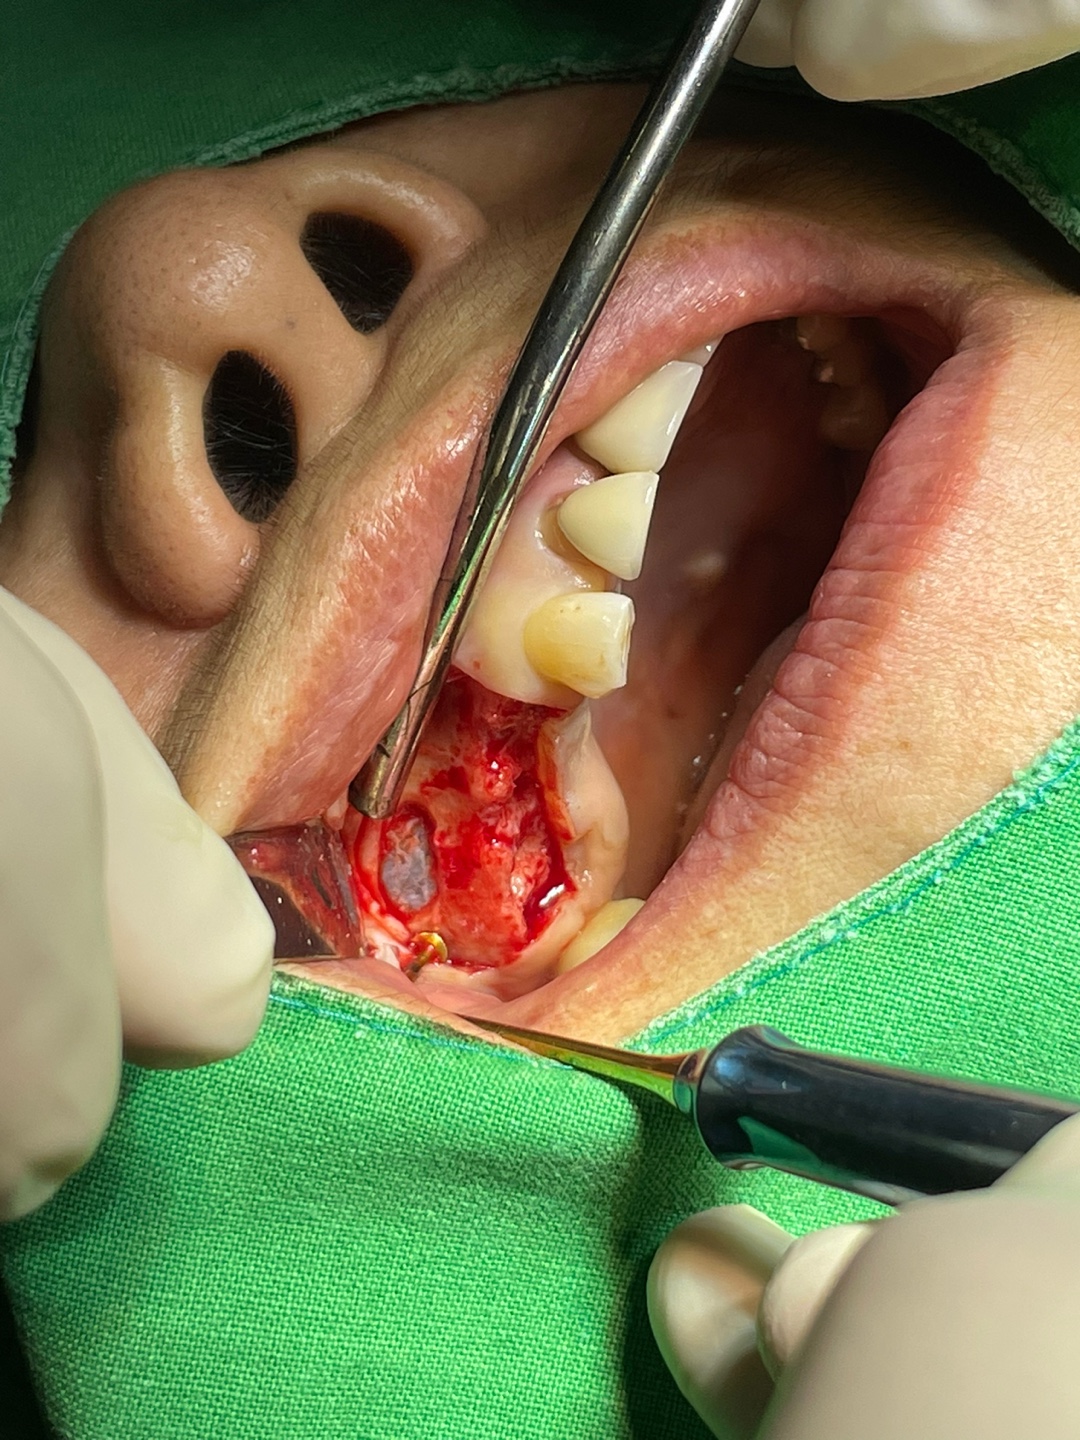

위의 사진을 본다면 구체적으로 어떤 방법으로 진행되는지 감을 잡을 수 있을 겁니다.

저는 상악동 거상술을 몇천회 이상 시행했지만

항상 저 막이 찢어지지 않게 최대한 조심합니다.

벌써 이십년 가까이 수술했지만 지금도 조금은 긴장된 마음으로 수술에 임하고 있습니다.

식립하는 임플란트는 제 경험상 상악동 거상술에 가장 성공율이 높았던 임플란트를 사용하고 있습니다.

모든 수술이 다 중요하지만 이 수술은 잘못을 바로잡기가 더운더 많은 시간을 요하기에 최대한 신중하게 수술에 임하고 있습니다.